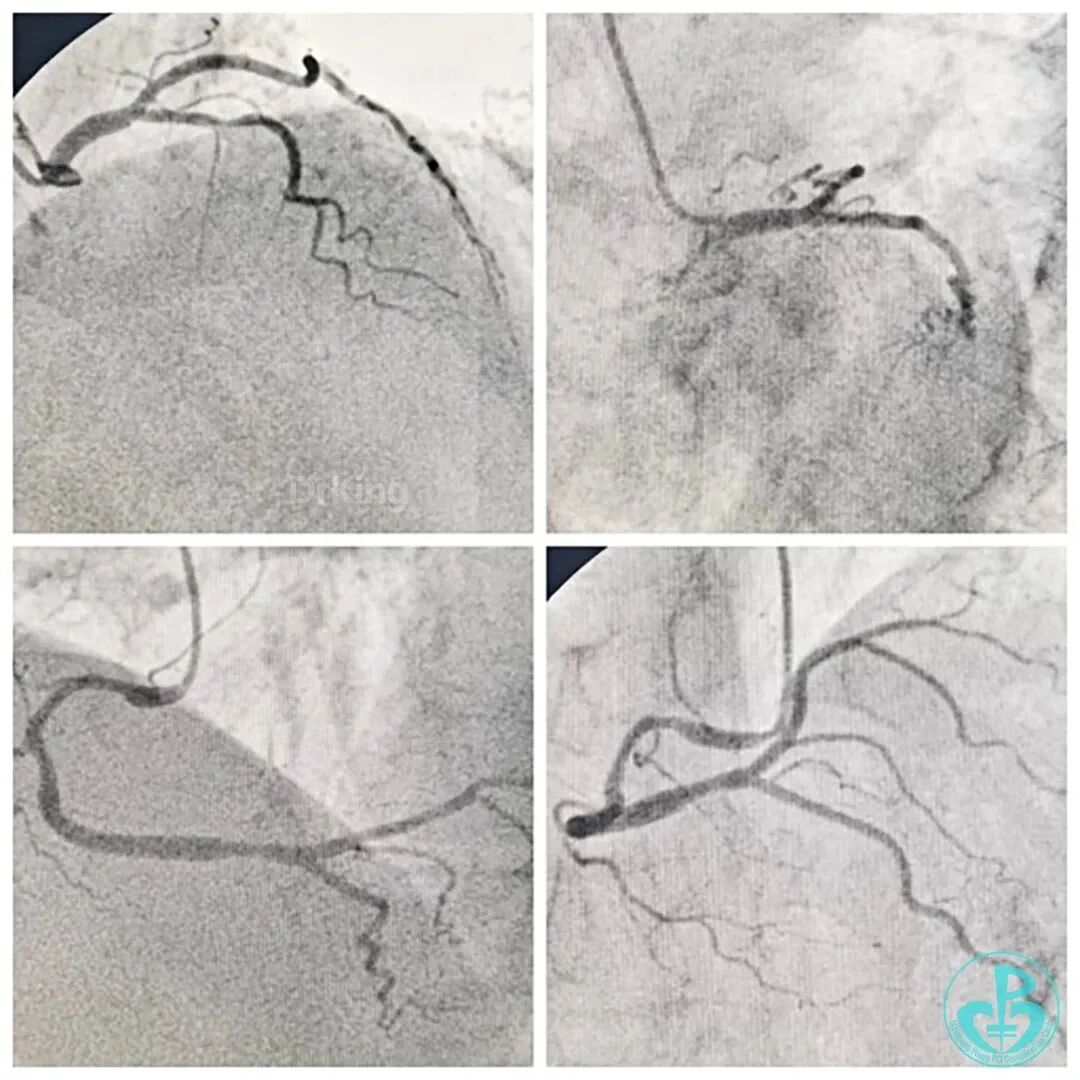

LAD开口完全闭塞,无(明确)残端,无同侧侧支供血,左侧仅剩较小的LCX及RI。RCA-PDA→S→m&dLAD侧支循环逆冠显影(RCA是心脏最主要的供血血管,相当于左主干;后文图有间隔支侧支显示)。

依次由远及近(PLA→dRCA-mRCA)全程DES,NCB优化扩张,RCA血流恢复,间隔支侧支循环恢复,病情趋于稳定。

导丝推进顺利,KDL交换为单腔微导管,逆向造影指引导丝送至LAD中远段真腔内,交换工作导丝,全程仅用了9分钟,IVUS精准、优化指导下PSP,DES 1枚,结果理想。